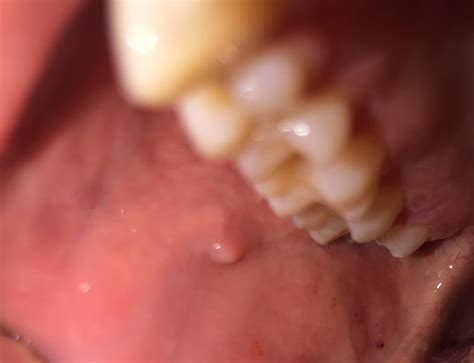

lump    cheek rdiagnoseme 2316×1776

lump cheek rdiagnoseme

epidermoid cyst  cheek 1000×1000

epidermoid cyst cheek